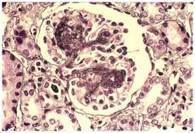

Glomerulonephritis - Wikipedia, The Free Encyclopedia

An increase in proteins passed from urine and decrease in blood protein levels, and an increase in circulating lipids; It is typically managed with corticosteroids and does not progress to chronic kidney disease. [2]:500 [3]:550. Focal segmental glomerulosclerosis Edit ... Read Article